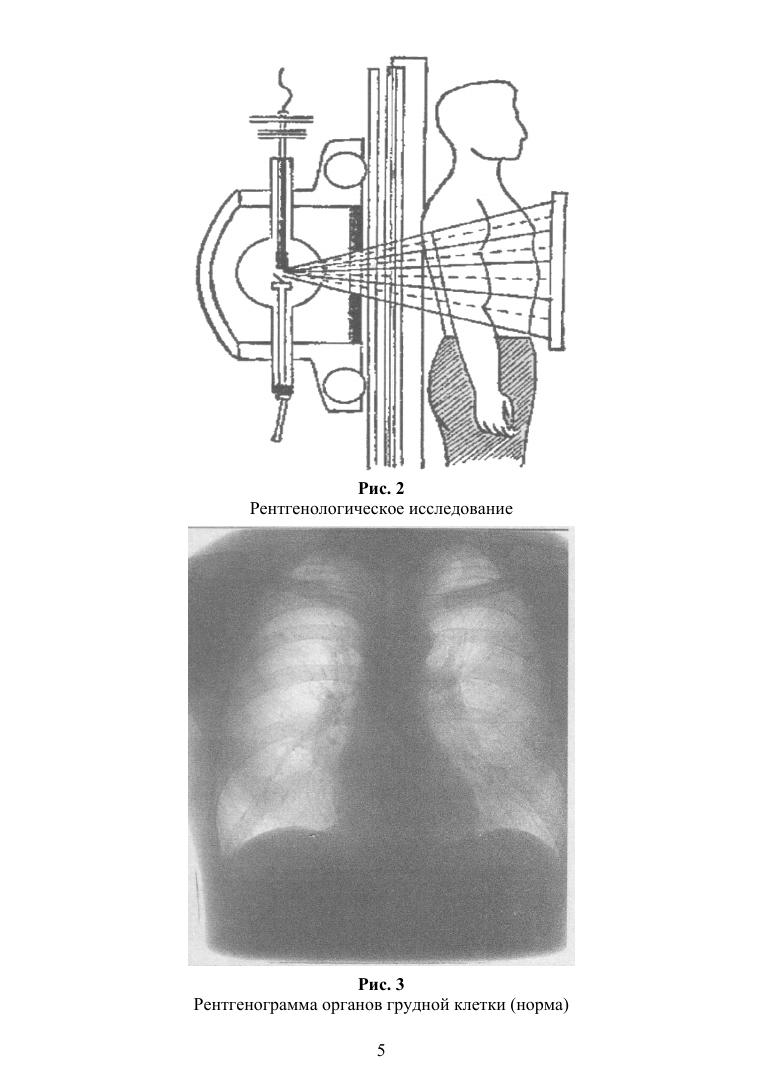

Рассмотрены основные инструментальные методы обследования, используемые при различных заболеваниях и состояниях. Указываются показания, противопоказания, осложнение, подготовка и методика проведения исследования, а также расшифровка полученных результатов. Соответствует современным требованиям Федерального государственного образовательного стандарта среднего профессионального образования и профессиональным квалификационным требованиям. Пособие будет полезно студентам медицинских колледжей по направлениям «Сестринское дело» (Сестринский уход при различных заболеваниях и состояниях) и «Лечебное дело» (Пропедевтика клинических дисциплин).